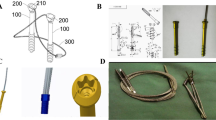

Recently, we invented a new cannulated screw with holes on the tail, which called Ding’s screw (Fig. 1). The goal of this study was to evaluate the biomechanical outcomes of this new technique (DSTBW) for the treatment of ITPPFs.

The inferior pole patellar fracture line was created. CSTBW and DSTBW surgical procedures were applied to fix the fracture by ProE 5.0 software (PTC Inc., Boston, MA). In the CSTBW group (Fig. 2a); fractures were fixed using traditional methods, as described in previous studies [9]. In the DSTBW group (Fig. 2b), the fracture was fixed according to the method described in our previous study [9].